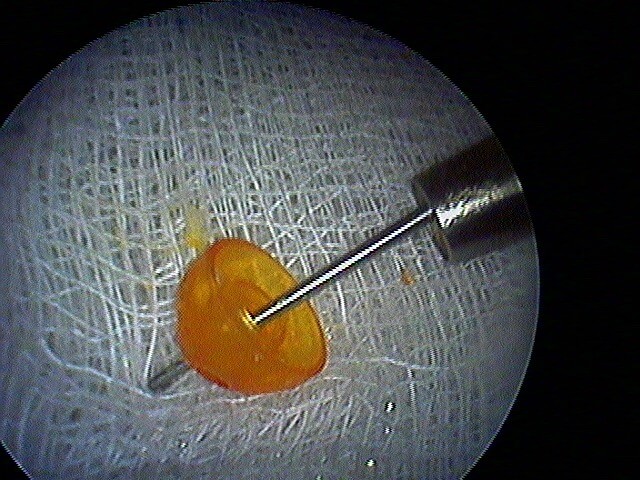

2/6 cholestéatome du CAE

Rare le cholestéatome du CAE, le tympan étant normal. Le diagnostic otoscopique est posé par la présence de squames et d'érosion osseuse. Ce sont des patients qui font des otites externes très rapprochées.